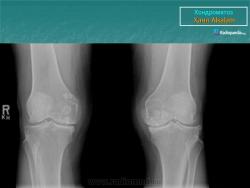

КСС. Хондроматоз внутрисуставной (синовиальный) 1. +

Хондроматоз внутрисуставной (синовиальный).

Хондроматоз

Хондроматоз внутрисуставной (синовиальный)

Хондроматоз суставов — хрящевая островковая метаплазия синовиальной оболочки

Синовиальный хондроматоз

Первичный синовиальный хондроматоз